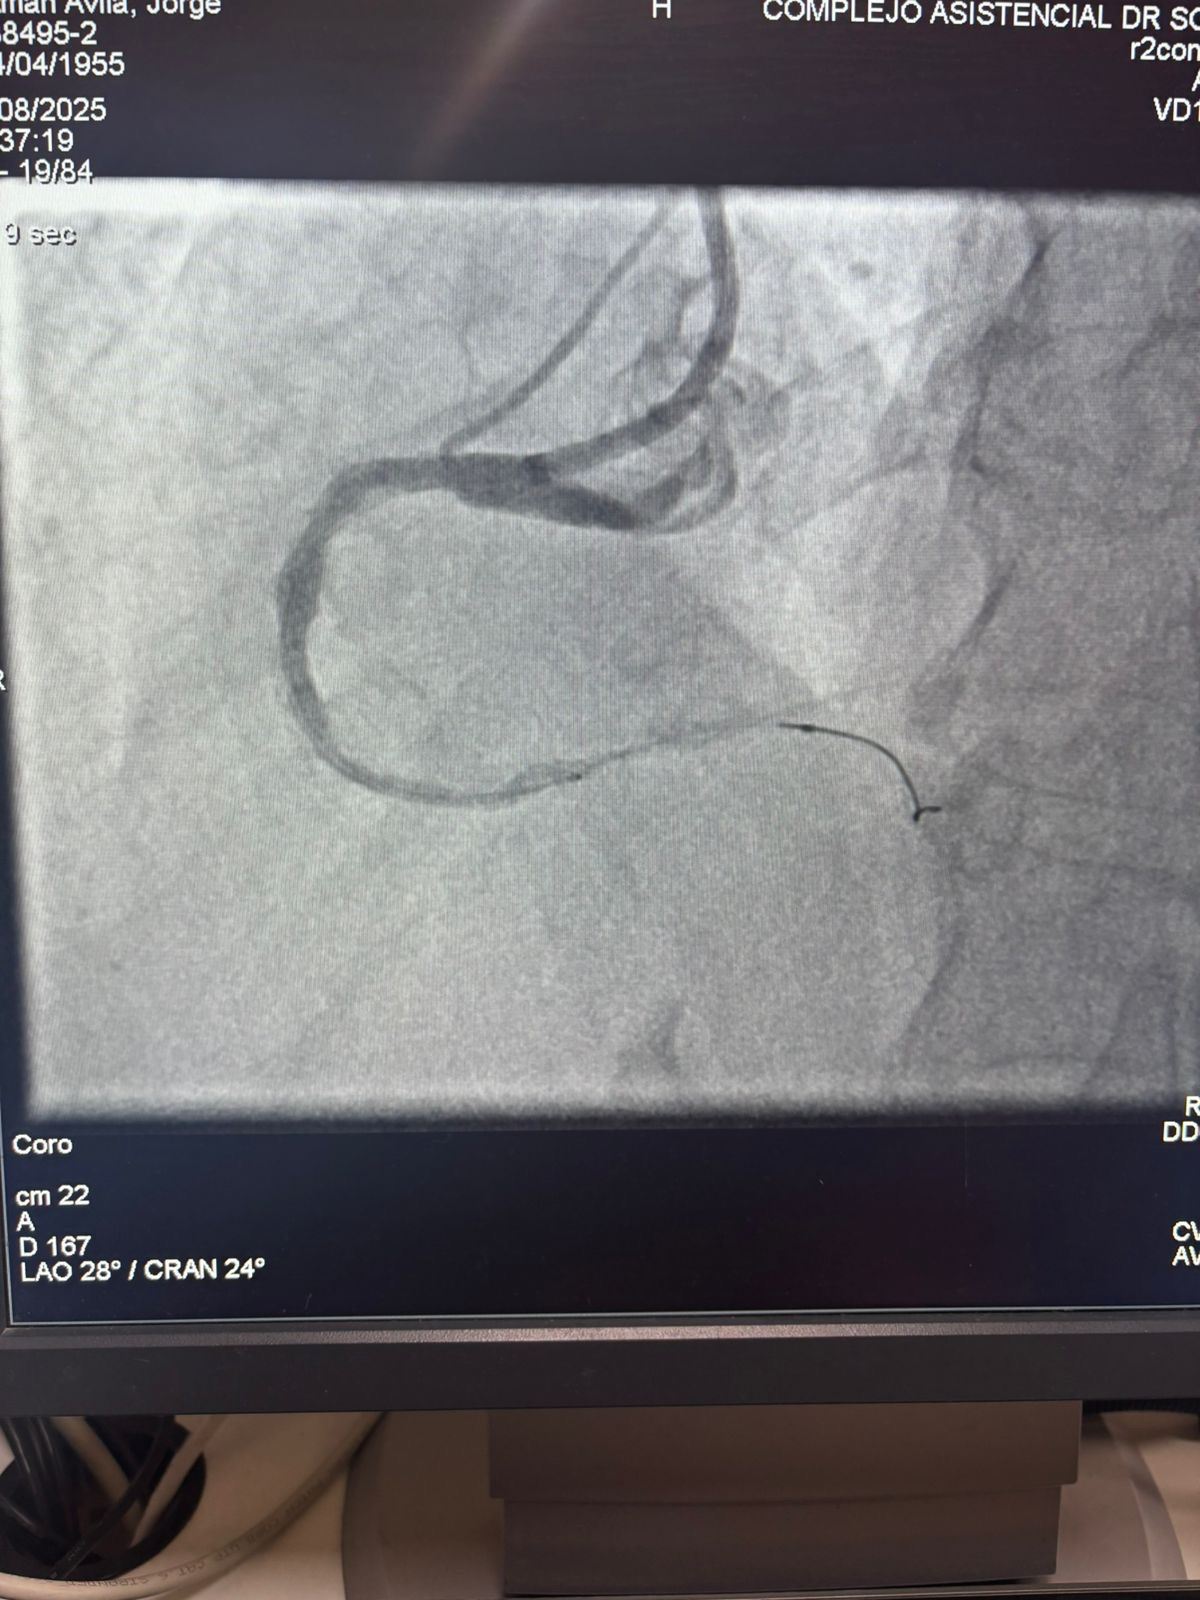

Siamo orgogliosi di condividere un caso straordinario dell'ospedale Sótero del Río, Cile, dove il Dr. Martín Valdebenito ha trattato con successo una lesione fortemente calcificata nell'arteria coronaria destra (prima curva) utilizzando il nostro sistema di catetere di dilatazione del palloncino Vesscrack Coronary IVL.

La procedura ha ottenuto risultati eccezionali, con la regione calcificata effettivamente incrinata e il flusso della nave ripristinato. Questo segna un'altra pietra miliare nell'espansione dell'accesso globale a soluzioni avanzate per la calcificazione coronarica complessa.

Il confronto tra le immagini angiografiche pre-procedura e post-procedura dimostra chiaramente il significativo impatto clinico della nostra tecnologia IVL.